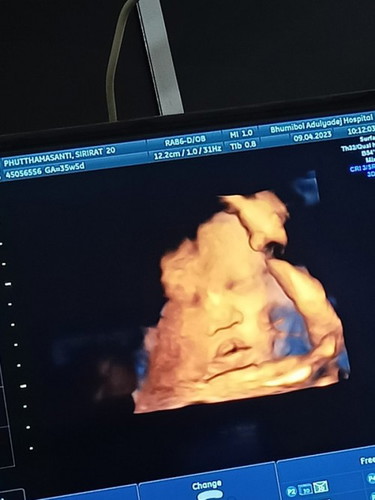

ในรุปดูเหมือนปากจะแหว่งเลยคะ แต่ถามหมอหมอบอกปกติ เลยไม่มั่นใจคะ#ขอบคุณล่วงหน้านะคะ #ขอคำแนะนำหน่อยค่ะ

ปกติค่ะ ซาวนด์ผ่านน้ำคร่ำภาพก็จะประมาณนี้

ถามหมอ3-4หมอก้บอกว่าไม่มีคะให้ดูที่ปากด้วยหมอบอกปากสามเหลี่ยมปกติคะ แต่รุปก้แอบกลัวคะ555